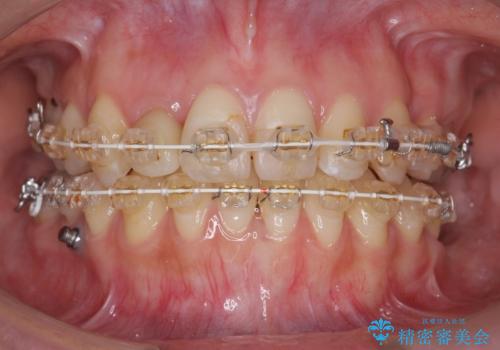

あきらめないで!!虫歯でボロボロでも大丈夫! 非抜歯矯正と虫歯、インプラント治療で見違える歯並びに。

- 矯正治療を希望して来院。

虫歯が多数、また奥歯も欠損してしまっていました。

左下の親知らず、左上の小臼歯が残根状態で一本抜いたほかは抜かずに矯正しました。